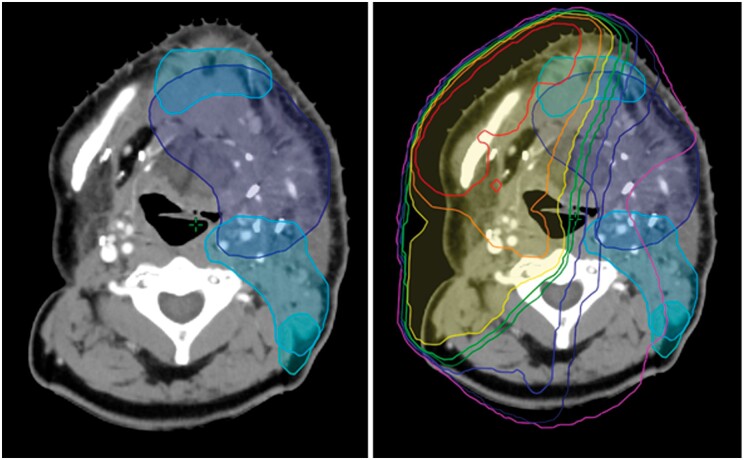

Abstract Image